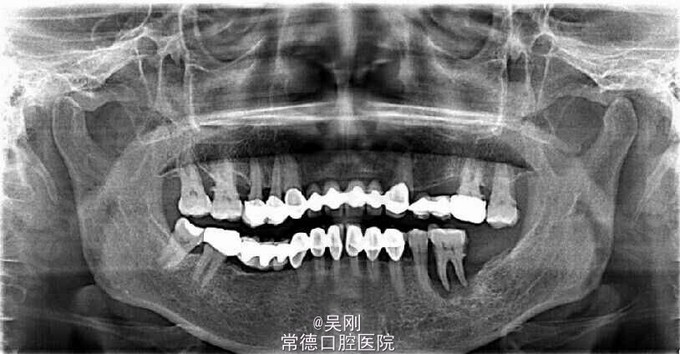

烤瓷牙使用出血。 五年前在外院做烤瓷桥修复,使用期间一直出血,半年前左上桥体折断。

烤瓷桥边缘不密封,探出血。 左上烤瓷桥桥体折断。

上下颌不良修复体。 磁性附着体修复。